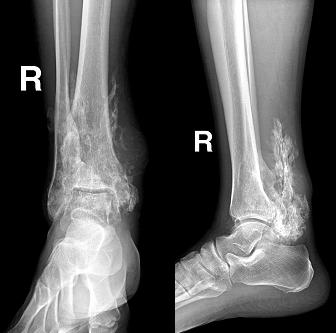

痛风性关节炎:尿酸代谢障碍,血尿酸增高,男性多见。;临床表现:潜伏期;急性发作期(1/3有X线改变);慢性期.;病理:滑膜增厚,肉芽组织,痛风结节

初期:关节肿胀,四肢关节均可,以第一跖趾关节为著.

晚期:关节骨端骨侵蚀性破坏,呈穿凿样,边界清楚。关节软骨破坏发生较晚,间隙变窄。关节旁或软组织内有痛风结节(可钙化)。

侵蚀性骨破坏

痛风结节